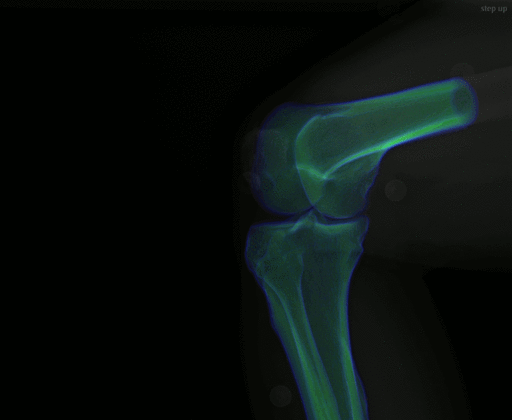

Radiostereometry uses two simultaneous x-ray recordings, and allows for high precision three-dimensional measurement of bones and implants.  With recent developments and digitalization, dynamic radiostereometric analysis can record bone, joint, and implant kinematics during movement.

A unique combination of high framerate, resolution, and precision makes dynamic radiostereometric analysis the perfect tool for measurements of dynamic bone and implant movements in orthopaedic patients.